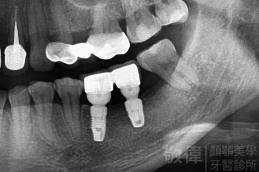

治療前-缺牙區X光   治療後-大臼齒X光

人工植牙/左下第1、2大臼齒植牙